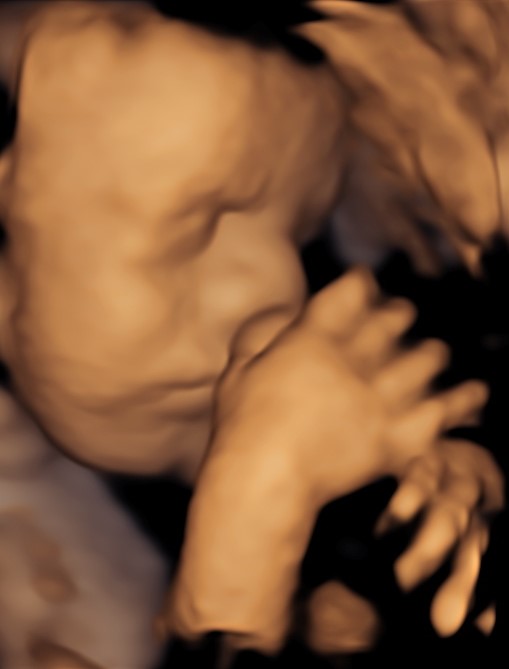

4D/5D/HD Ultrasound Gallery

Gallery